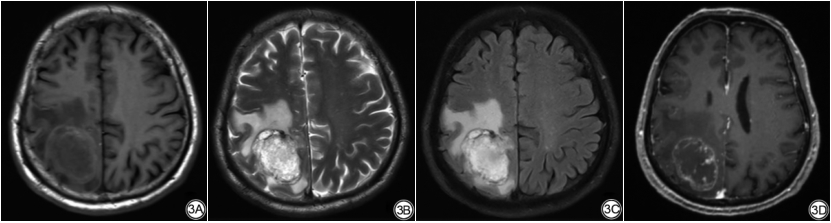

该研究共包括121名患者(61名HGG和60名SBM)。其中60例SBM患者中原发性肺癌22例,原发性乳腺癌4例,原发性食管癌2例,原发性结直肠癌1例,原发性前列腺癌1例,原发性鼻咽癌1例,不明原因癌症29例。本研究的数据显示,HGG和SBM之间没有显著的性别差异(P=0.293)(表1)。从表1可知,SBM患者年龄较大[SBM组为(58.02±9.89)岁,HGG组为(49.92±16.07)岁,P=0.001]并且更有可能位于幕下区域(SBM组为10/60,而HGG组0/61,P=0.001)。如图2、图3所示分别为一例经组织病理学证实为HGG和SBM的MRI示意图。